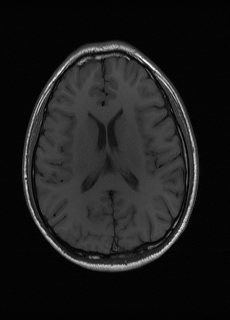

As we observe from the right image in Fig. 2, our BRM, both from MIMO and SISO settings, predicts the performance of dedicated models with a high correlation. We further choose the best three , and perform the last stage of fine-tuning accordingly to (6). A visual evaluation on real data is shown in Fig. 3. For simulated data, please refer to the Supplemental Material section.

Base on the best performing , we perceive that among , , and FLAIR, the results are best when is sampled the most. We suggest that this makes intuitive sense as images provide the best contrast out of the three sequences, which can compensate for the details lost in other images. The same observation can be made on the simulated data, where both and FLAIR show good contrast. When the time setting is changed to non-uniformity, we can see that our search for the best sampling strategy reflects the change. is sampled more as a result of faster acquisition time, while is still sufficiently sampled.

| Sequence | LR | SISO | MIMO | MIMO tuned | GT |

|---|---|---|---|---|---|

(a) 34.38/0.9371

(a) 34.38/0.9371

|

(b) 42.42/0.9883

(b) 42.42/0.9883

|

(c) 44.60/0.9920

(c) 44.60/0.9920

|

(d) 45.50/0.9940

(d) 45.50/0.9940

|

(e) PSNR/SSIM

(e) PSNR/SSIM

|

|

(f) 29.74/0.8903

(f) 29.74/0.8903

|

(g) 36.25/0.9734

(g) 36.25/0.9734

|

(h) 36.42/0.9752

(h) 36.42/0.9752

|

(i) 37.70/0.9832

(i) 37.70/0.9832

|

(j) PSNR/SSIM

(j) PSNR/SSIM

|

|

(k) 39.89/0.9311

(k) 39.89/0.9311

|

(l) 43.94/0.9864

(l) 43.94/0.9864

|

(m) 44.74/0.9883

(m) 44.74/0.9883

|

(n) 45.49/0.9894

(n) 45.49/0.9894

|

(o) PSNR/SSIM

(o) PSNR/SSIM

|